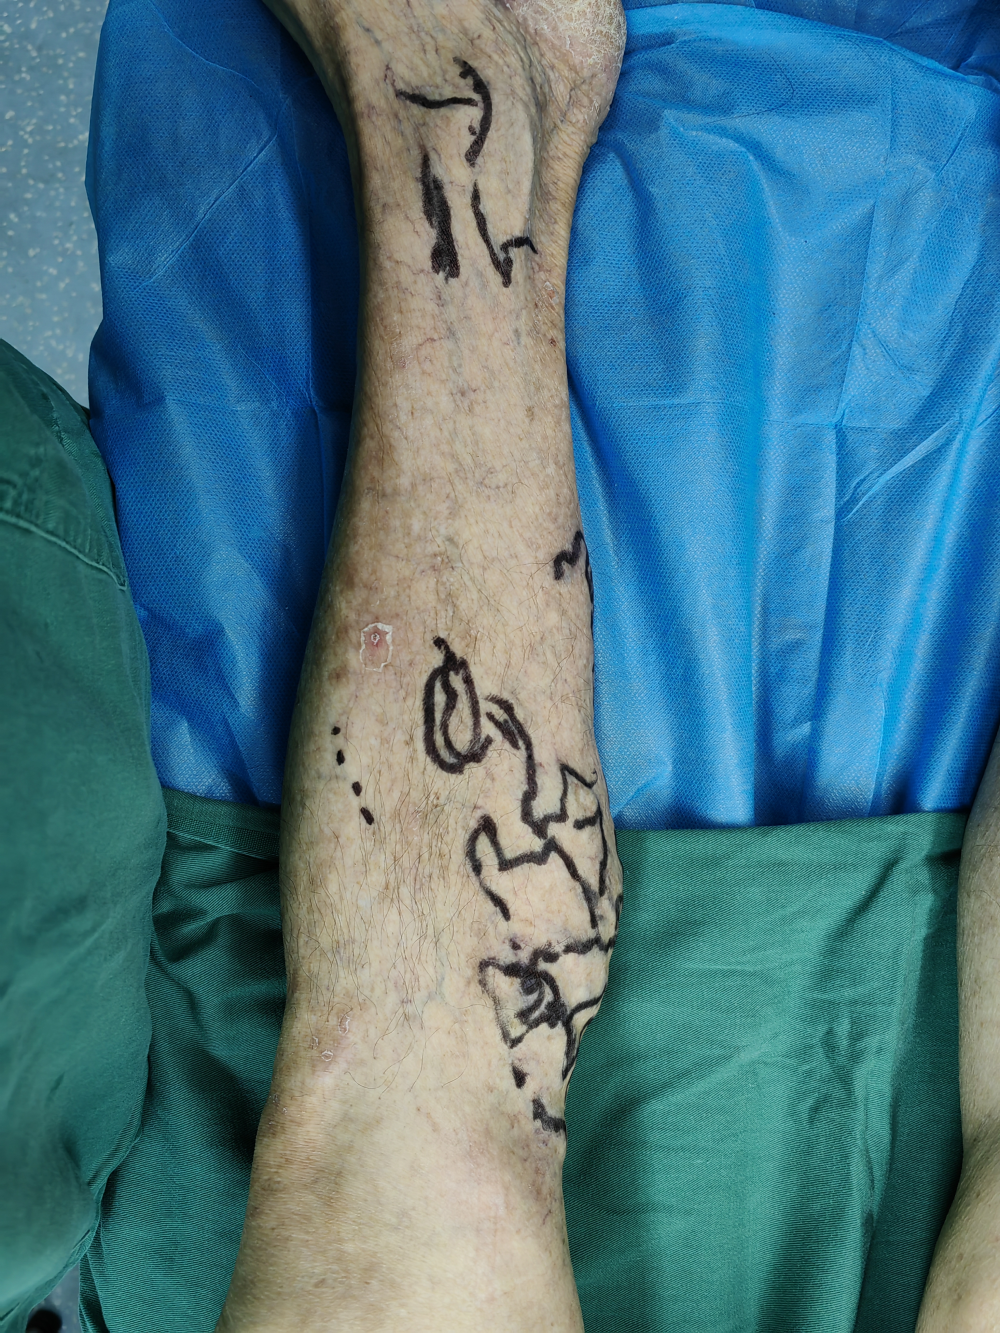

二、 下肢靜脈微創手術

下肢靜脈曲張(zhāng)為常見病及(jí)多發病,臨床表現主要為下肢血管迂曲(qǔ)、下肢腫脹(zhàng)、疼(téng)痛、局部皮膚(fū)色素(sù)沉著、嚴重時出現局部潰瘍、潰爛。對於有嚴重臨(lín)床表現者均需(xū)要手術治療。傳統手術為大隱靜脈高位結紮+主幹剝脫(tuō)+曲張靜(jìng)脈剝脫,相比微創手術其缺點(diǎn)是創傷大、恢複慢、下肢皮膚麻木感、不美觀等。我院(yuàn)外(wài)二科自2022年底始常規開展下肢靜脈微創手術,運用穿刺技術進行血管腔內消融閉合,硬化劑注射(shè)閉合曲張血管,從而達到傳統手術一樣效果,其優點為無切口、損(sǔn)傷小、恢複(fù)快、術後疼痛輕微(wēi)、無明顯(xiǎn)皮膚麻木感(gǎn)、美觀等。下肢靜(jìng)脈曲張主要危險因(yīn)素有:重(chóng)體力勞動、長(zhǎng)時間站(zhàn)立工作、體型粗(cū)大、妊娠(shēn)、長時(shí)間座位工作等。預防下肢靜脈曲(qǔ)張措施有(yǒu):改變工作方式,如(rú)需長時間站立或者座位工(gōng)作者,可以穿靜脈曲(qǔ)張彈力襪;保持良好生活習慣,堅持適當體育鍛煉(liàn)等。外二科現常規開展血管外科相關(guān)手術(shù),如下肢靜脈曲張微創(chuàng)手(shǒu)術、下肢靜脈血栓相關手(shǒu)術治療、血管瘤/血管(guǎn)畸形介(jiè)入治療、下肢動脈常規介入手術、內髒血管病變相關介入手術、內髒出血栓塞術(shù)等(děng)。

手術中